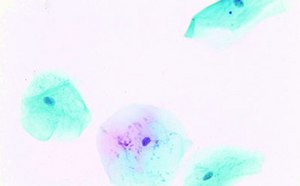

细胞学染色剂

选择我们的全系列染色剂和试剂产品用于研究和临床样本细胞化学染色的所有步骤。